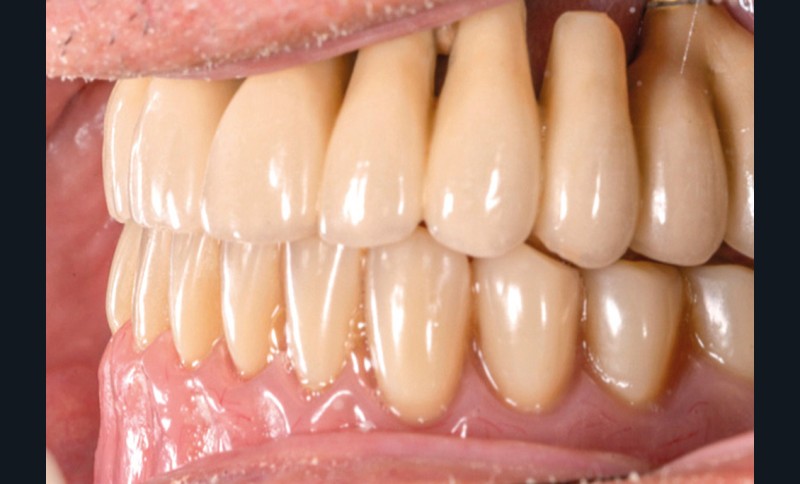

Dans le cas clinique présenté dans cet article, le patient édenté total bimaxillaire se plaint d’une gêne importante et d’une insatisfaction de son sourire en lien avec un plan d’occlusion prothétique inadapté (fig. 1 et 2).